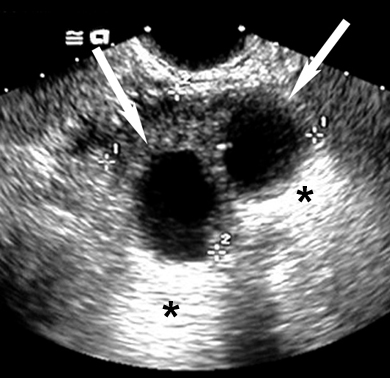

Simple Anechoic Renal Cysts

Cyst (arrow).

Through transmission (asterix).